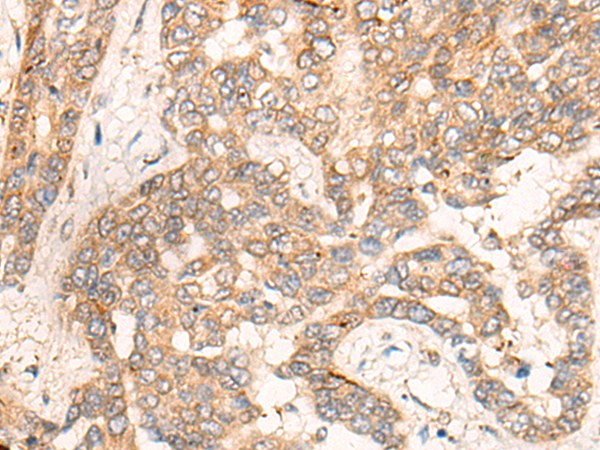

IHC positive control: |

Human liver cancer and Human gastric cancer |

IHC Recommend dilution: |

25-100 |